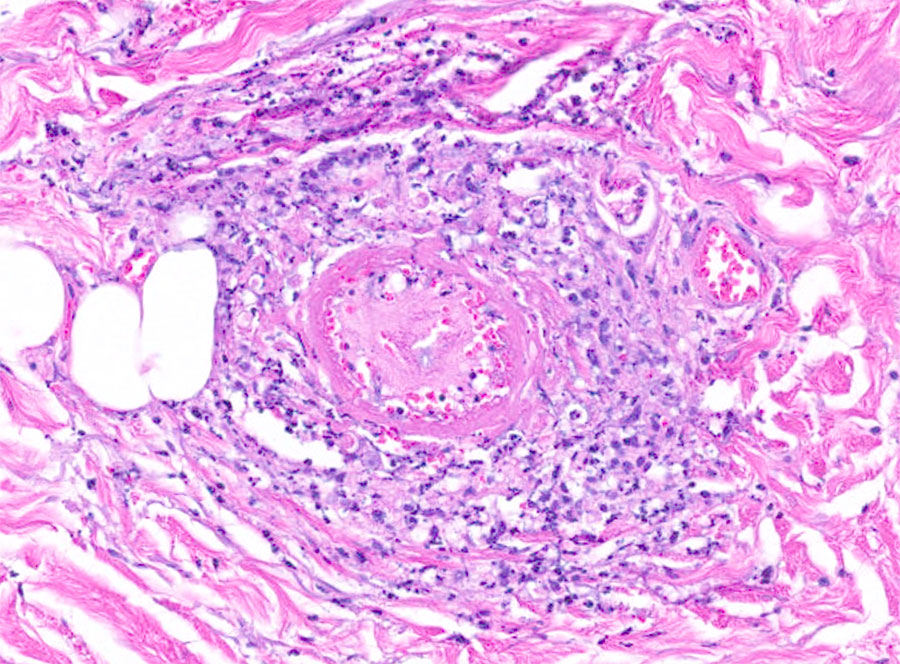

Disseminated Acanthamoeba Infection with Necrotic Skin Lesions and Granulomatous Vasculitis, United States

Figure 3

Figure 3. Periodic acid–Schiff positive histiocytoid cells from a patient with disseminated Acanthamoeba infection with necrotic skin lesions and granulomatous vasculitis. Magnification ×200.